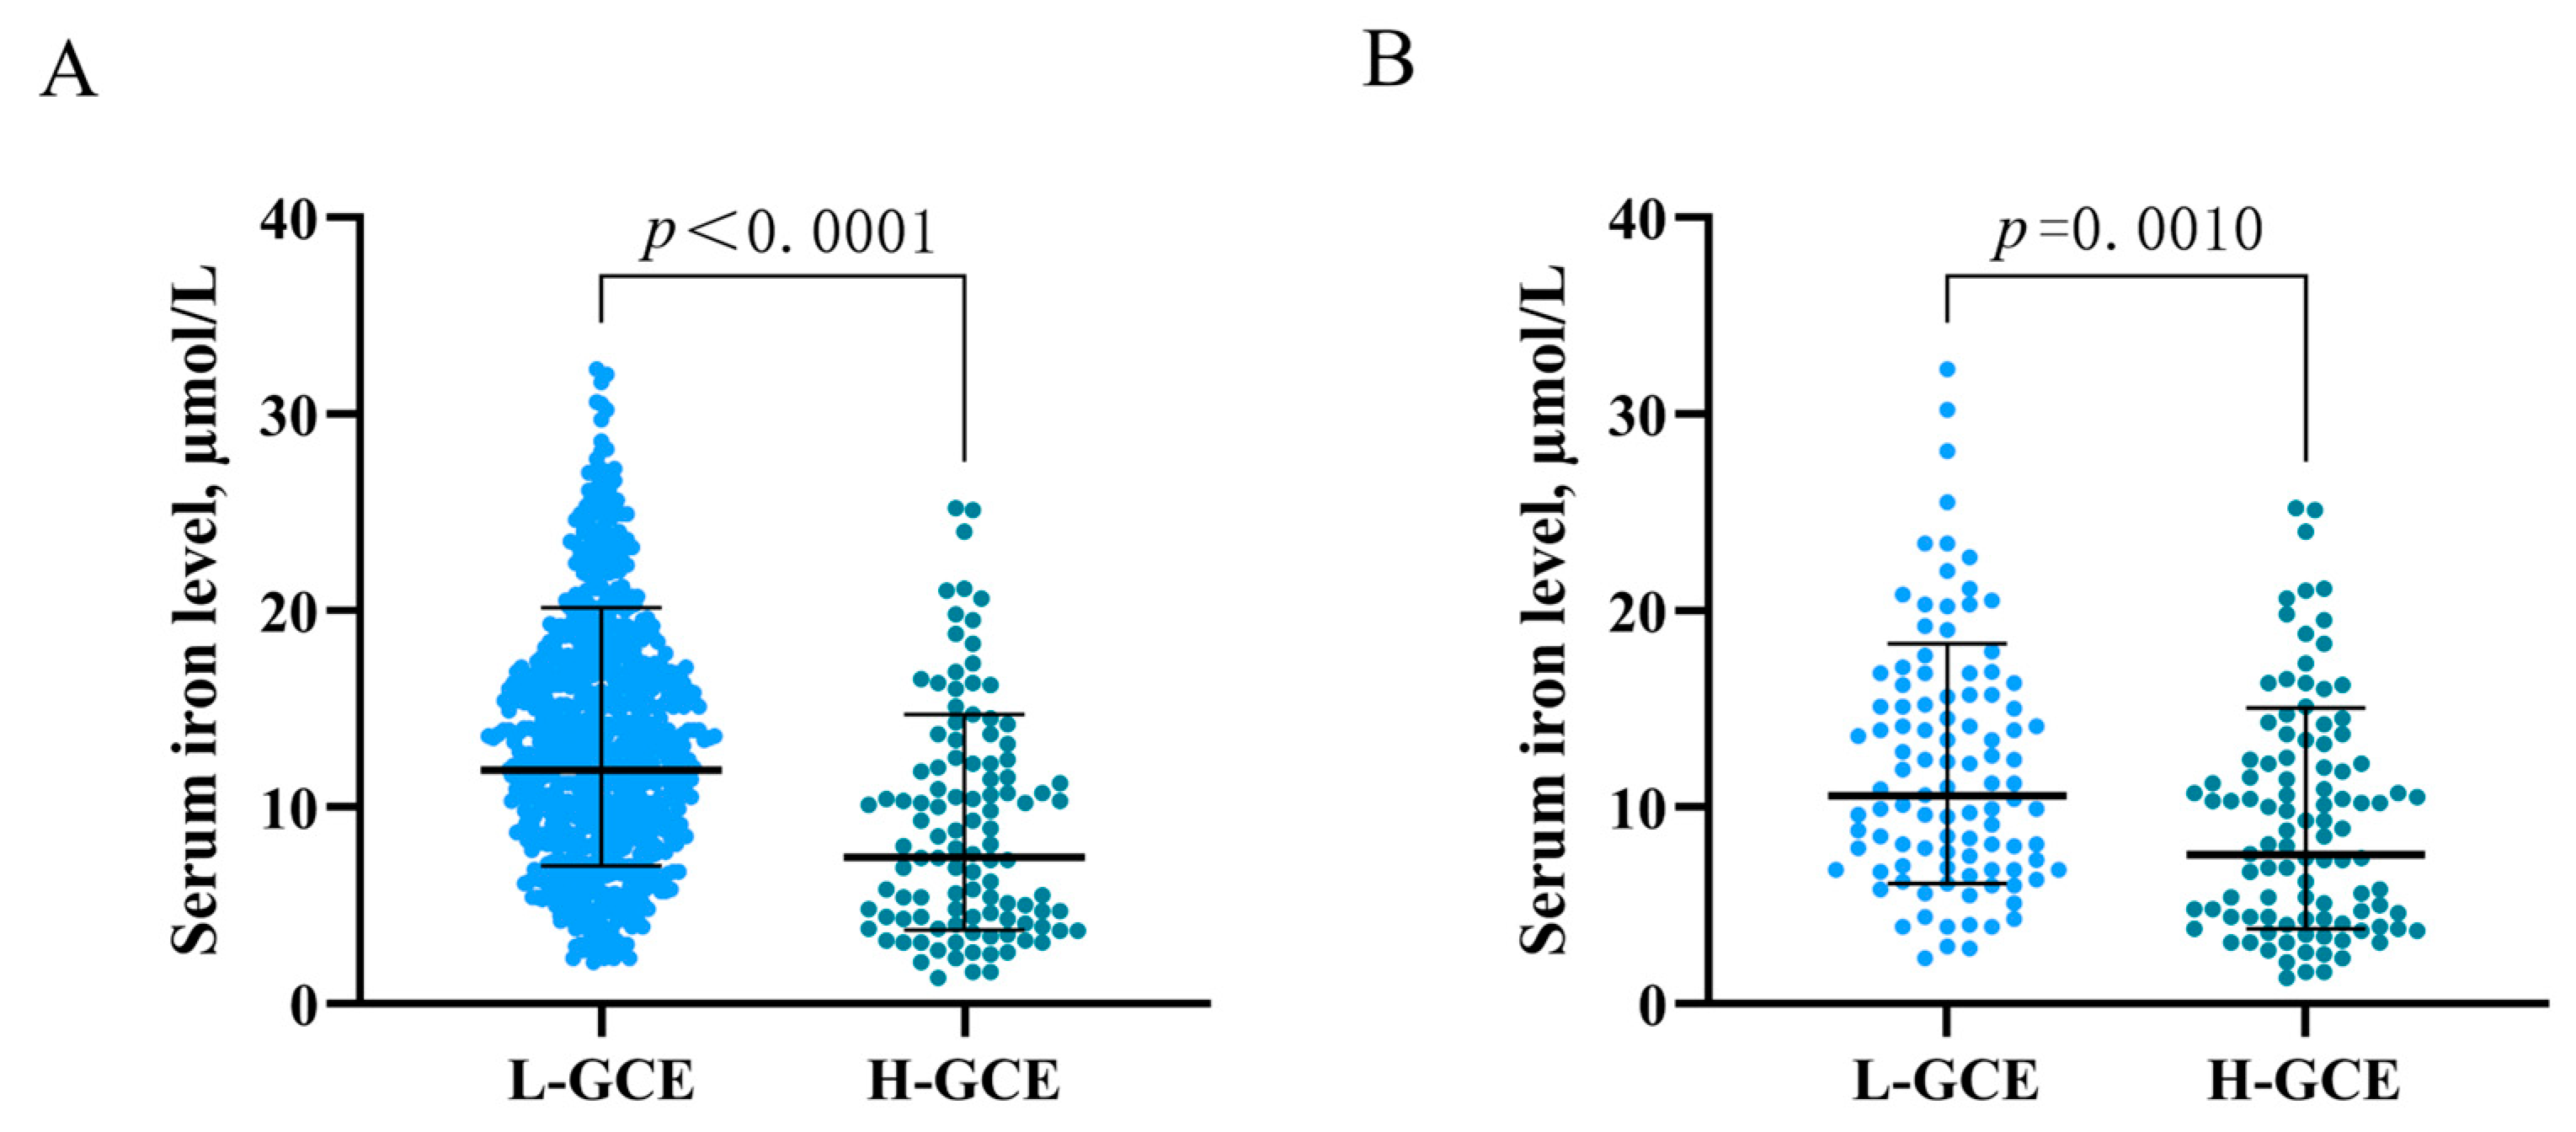

4.2. Risk Factors for H-GCE

4.3. Association of Serum Iron with HHgrade and mFisher Grade

| Serum iron, µmol/L | 9.186 (5.726) | 13.425 (6.139) | <0.001 |

| Serum iron, µmol/L | 9.358 (5.761) | 12.146 (6.258) | 0.001 |